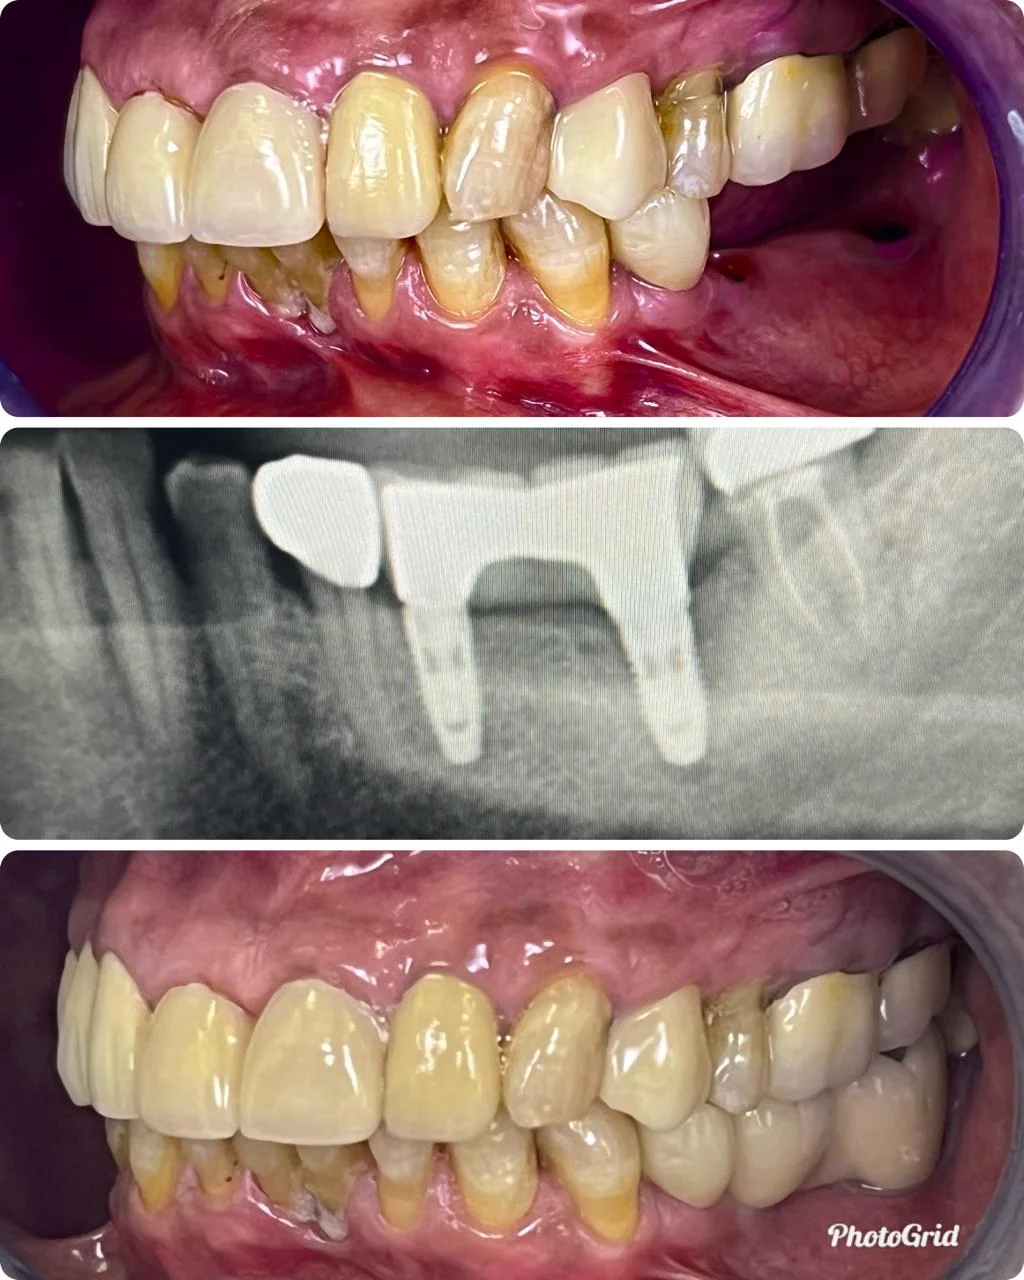

Showing Our Expertise In Dental Implantology